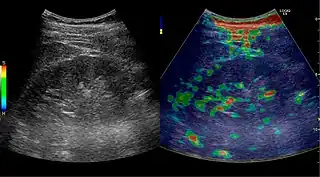

CEUS, image fusion and elastography

Contrast-enhanced ultrasound (CEUS) can evaluate microvasculature, which color Doppler US is unable to detect. In renal US examination, CEUS can be used to differentiate tumor and pseudotumor, such as prominent columns of Bertin. Pseudotumors enhance as adjacent renal tissue. The use of CEUS is recommended in special cases to distinguish between cystic and hypovascularized solid lesions, to characterize complex cysts, abscesses, traumatic lesions and ischemic lesions.[1]

Figure 30. Renal cell carcinoma successfully treated with thermal ablation, as no contrast enhancement is seen.[1]

Solid malignant tumors in the kidney do not exhibit specific enhancement patterns like some liver lesions, and no valid enhancement criteria between benign and malignant renal lesions have been proposed. However, CEUS is used in some patients after ablation of renal cell carcinoma to evaluate contrast uptake in the treated area (Figure 30).